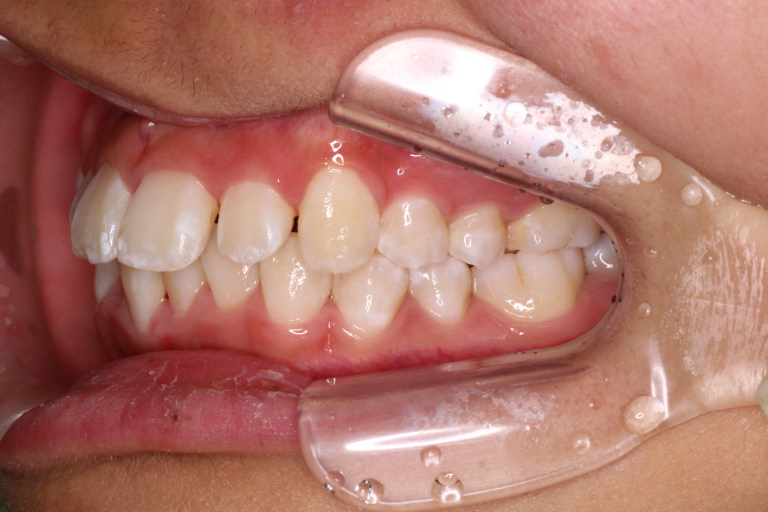

初診時の写真です。

前歯にはがたつき(叢生)がみられ、奥歯は上の歯と下の歯が1歯対1歯で噛んでいることがわかります。

つまり出っ歯の噛み合わせです。

診断:上顎前突・前歯部叢生